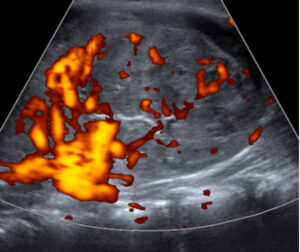

Ecografia renal

Eco Doppler renal